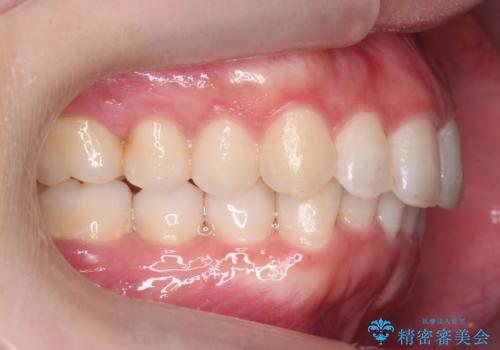

前歯をさげたい 歯を抜かずに マウスピース矯正で治したい

- 上の前歯が出ているとのことで来院。

歯を抜かずに、上の奥歯を後ろにさげつつ上の前歯を小さく少し削る処置を行い前歯の角度を修正しました。

右上下の奥歯もすれ違い咬合も、治療で改善しています。

下の前歯が生まれつき3本でしたので上下の正中は合わない仕上がりとなります。